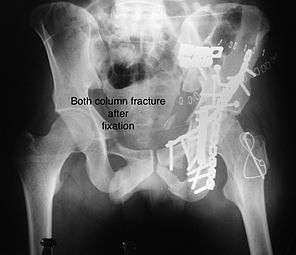

Combined both column fractures

These are the most complex injuries. Here the weight bearing roof or dome of the acetabulum is a floating piece. This adds to complexity of management.

Cause: Combination of forces acting on the hip though the femoral head

Associated injury: Sciatic nerve, may be femoral nerve or vessels

How to diagnose: all three x-ray views plus CT scan is a must for diagnosis and management of this complex injury

Treatment: like any other acetabular fracture, if the femoral head is dislocated out of the socket, early reduction into socket is a priority. Non operative treatment rarely gives satisfactory result. If the patient is unfit to undergo major surgery due to any reason, longitudinal traction to achieve secondary congruence of hip may help to restore hip function, though partially.

Surgical management is ideal. The choice of approach rests with the surgeon, but going from front, or anterior approach is preferred. The posterior injury may be tacked with anterior approach by experienced surgeon.

Post-surgery treatment: depending on the stability achieved, the person may be allowed standing and walking with help of support for about six to eight weeks.

Full function may return in about three months.

Complications: Injury to the femoral head, stoppage of blood supply to femoral head at the time of accident or during surgery may occur. Sciatic nerve may get damaged at the time of injury or during surgery. Anterior approach may cause damage to lateral cutaneous nerve of the thigh, injury to femoral nerve of femoral vessels may occur.

Deep vein thrombosis and pulmonary embolism are other complications that may occur in any type of injury to the acetabulum.